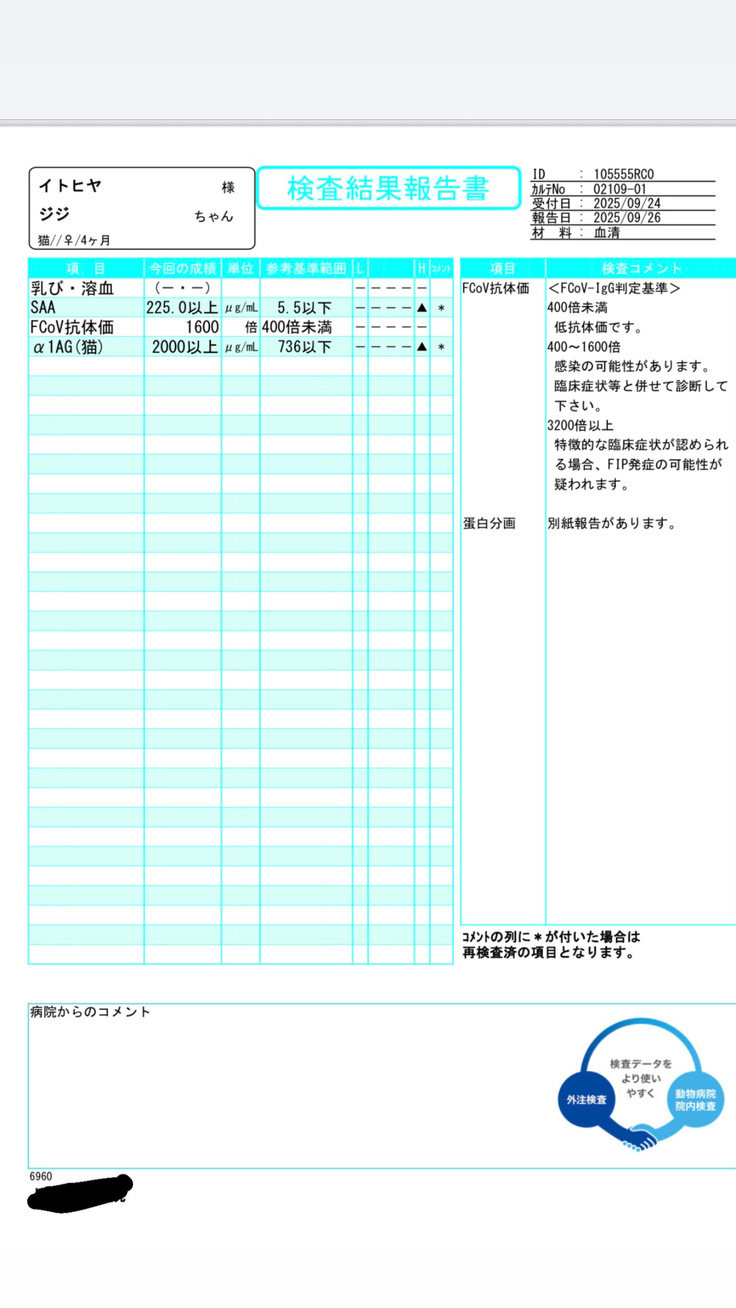

すぐに血液検査など詳しい検査をしていただき、出た結果です。

タンパク質からの計算式に基づいて、この時点でおそらくFIPで間違いないだろうとの診断でした。

そして詳細の検査の結果、9/26、正式にFIP(Wetタイプ)と診断を受けました。